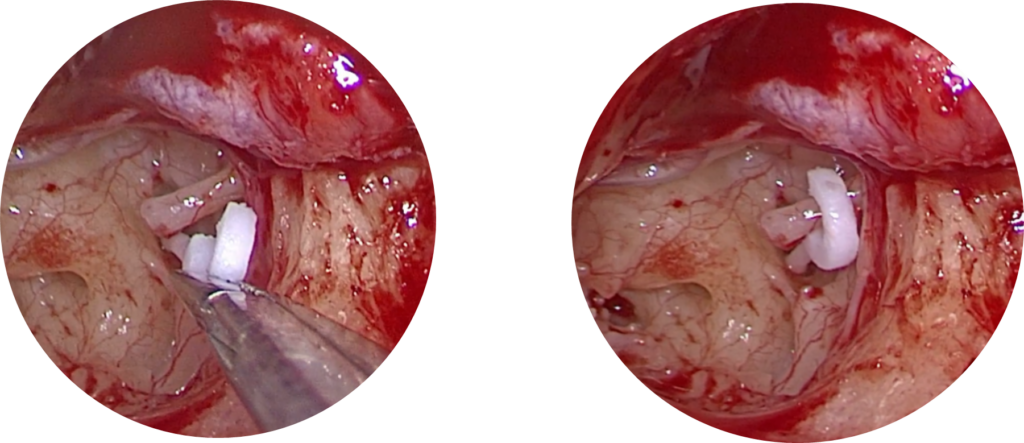

Vue endoscopique peropératoire de l’oreille moyenne :

Ablation de l’étrier bloqué

Mise en place d’une prothèse en fluoroplastic (piston)